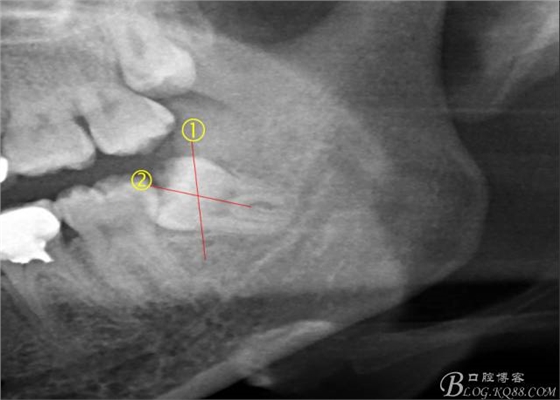

先分析智齒的情況,口內(nèi)直觀是半個(gè)牙尖都沒露出來,差一點(diǎn)就完全埋伏了。磨牙后墊的可操作面積中規(guī)中紀(jì),X全景片示三類阻生,根冠比例是1:1,非融合根,近中根壓下頜管。

640 (6).jpg

術(shù)前分析:智齒分牙的方法不少,但個(gè)人感覺都與這十字分牙法差不多,大多數(shù)阻生齒的分牙都在此基礎(chǔ)上進(jìn)行改進(jìn)。

640 (7).jpg